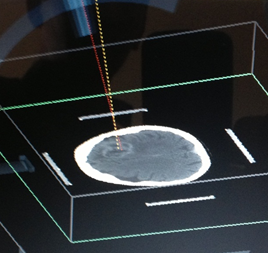

1) MARCO ESTEREOTAXIA: Marcación estereotáctica para lesiones profundas , craneotomias guiada por estereotaxia y/o asistidas por Neuronavegación. (Incluirá el equipo)

VI. CIRUGIA FUNCIONAL , ESTEREOTAXIA Y EPILEPSIA

Se prestará la asistencia para la alternativa terapéutica en casos de enfermedades refractarias a tto médico, cirugía en casos de movimientos

anormales (parkinson) , temblor esencial mediante la implantación de estimuladores.